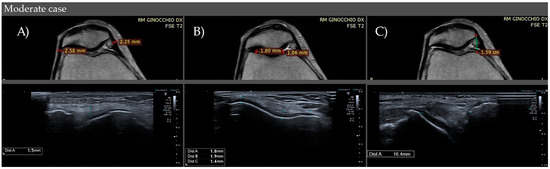

| CONTROLS | Medial Retinaculum | 0.9–1.0 mm (IQR) (M1) | 0.9–1.1 mm (IQR) (M1) |

| Lateral Retinaculum | 0.7–1.0 mm (IQR) (M0.9) | 0.9–1 mm (IQR) (M1) | |

| CASES | Medial Retinaculum | 1.3–2.6 (IQR) (M2.1) Mild: <1.3 mm Moderate: 1.3–2.6 mm Severe: >2.6 mm | 1.5–2.8 (IQR) (M2.3) Mild: <1.5 mm Moderate: 1.5–2.8 mm Severe: >2.8 mm |

| Lateral Retinaculum | 1.2–2.5 (IQR) (M0.9) Mild: <1.2 mm Moderate: 1.2–2.5 mm Severe: >2.5 mm | 1.3–2.5 (IQR) (M2.2) Mild: <1.3 mm Moderate: 1.3–2.5 mm Severe: >2.5 mm | |

| CONTROLS | Medial Thickness | 2.8–4.7 mm (IQR) (M4) | 2.9–4.5 mm (IQR) (M3.8) |

| Lateral Thickness | 3.3–5.1 mm (IQR) (M4.45) | 3.0–4.8 mm (IQR) (M4.2) | |

| CASES | Medial Thickness | 1.5–2.3 (IQR) (M1.8) Mild: >2.3 mm Moderate: 1.5–2.3 mm Severe: <1.5 mm | 1.2–2.1 (IQR) (M1.55) Mild: >2.1 mm Moderate: 1.2–2.1 mm Severe: <1.2 mm |

| Lateral Thickness | 1.8–2.65 (IQR) (M2.3) Mild: >2.6 mm Moderate: 1.8–2.6 mm Severe: <1.8 mm | 1.65–2.5 (IQR) (M2) Mild: >2.5 mm Moderate: 1.6–2.5 mm Severe: <1.6 mm | |